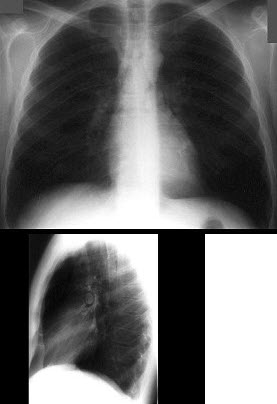

116、单项选择题

男,75岁,胸痛,咳嗽半年,气逼,多年前曾因黑色素瘤手术,胸片如图,最可能的诊断是()